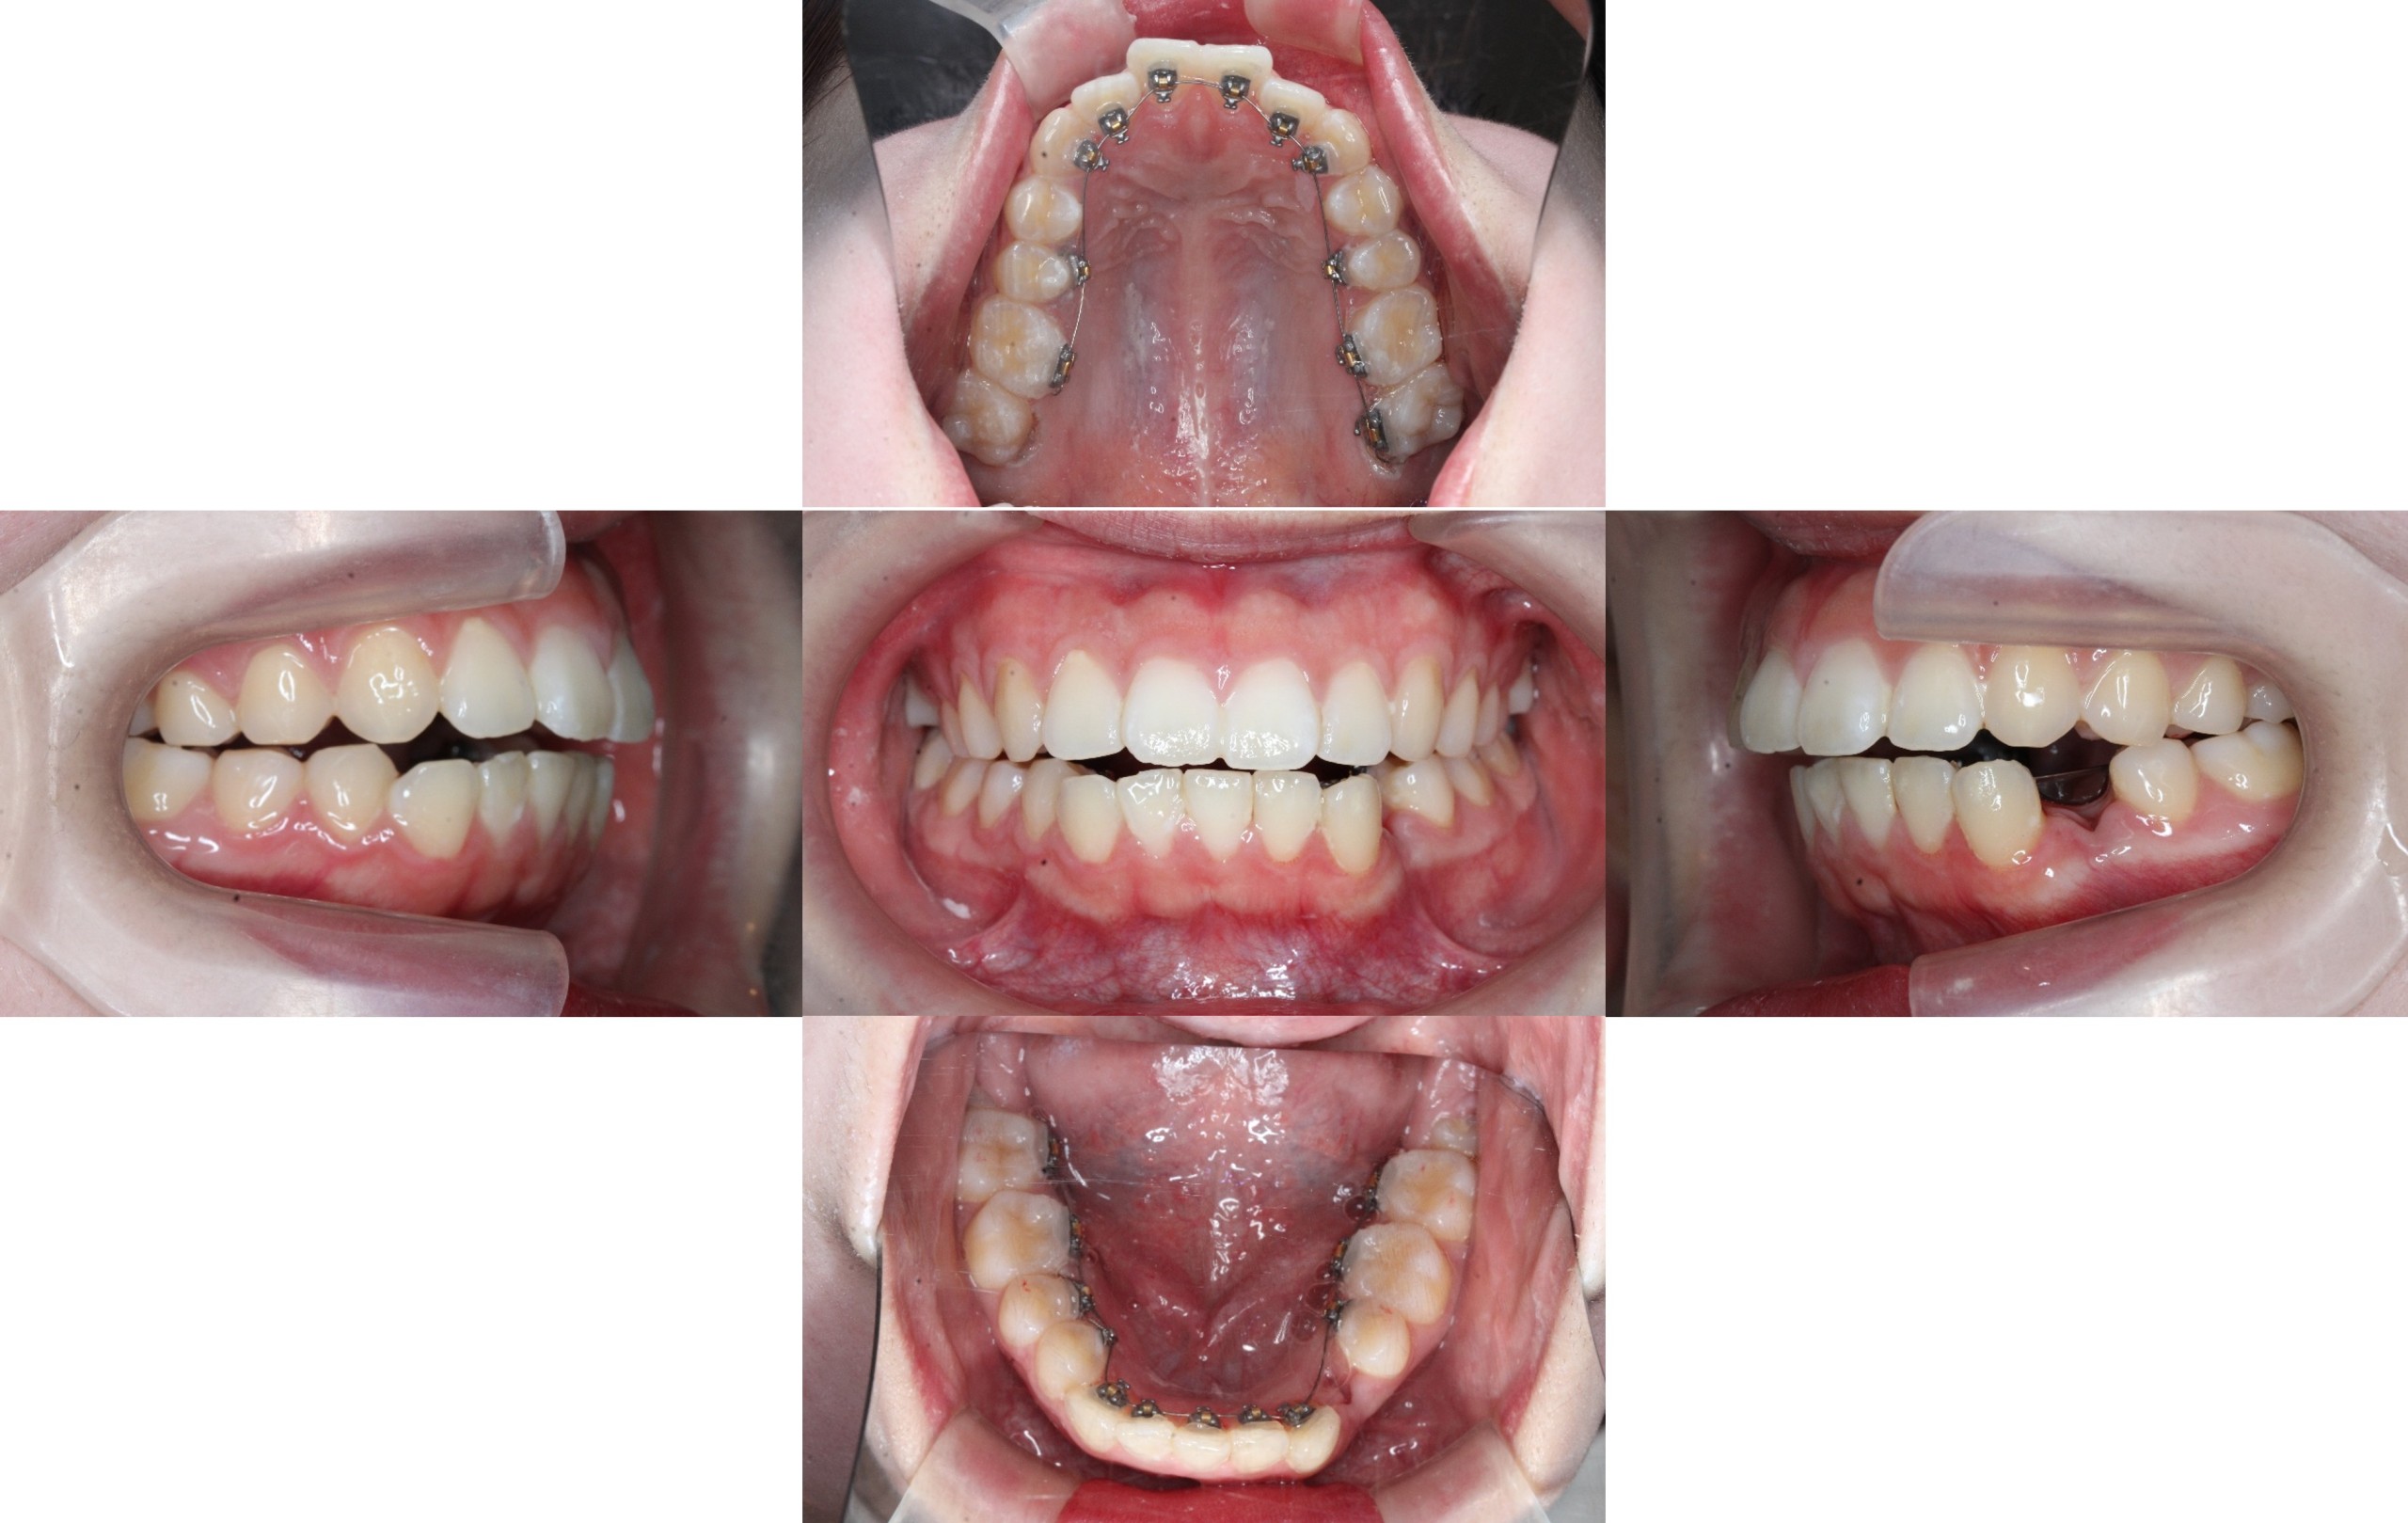

装置装着